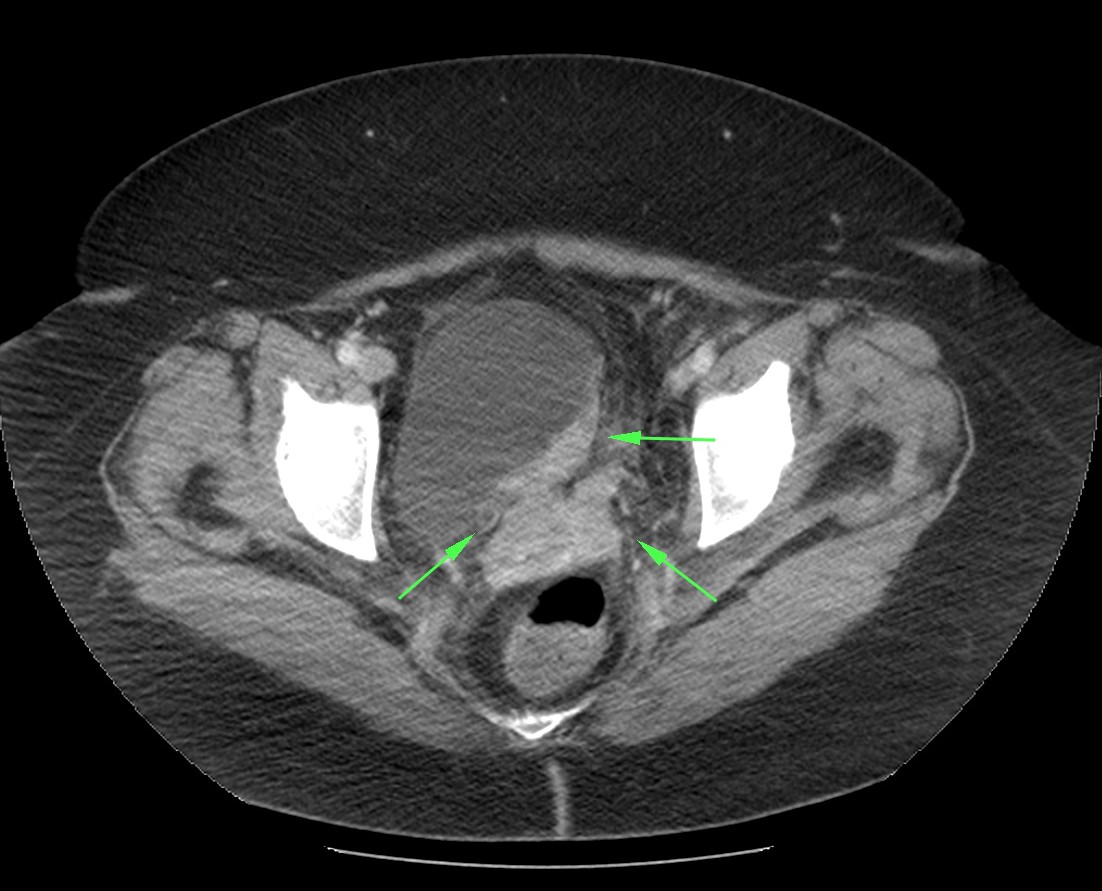

Paciente de 59 años con antecedentes personales de Cá de vejiga.

Se le realiza una Uro-Tc por seguimiento al año, aunque en esta ocasión el paciente refiere episodio de hematuria.

Tras el tratamiento de la recidiva y nefrostomía para la hidroureteronefrosis, vuelve acudir al hospital a los 9 meses por episodio de dolor en FD y malestar general. Se realiza una ecografía de urgencias.

Se realiza nueva TC bifásico abdominopélvio y Uro TC.

- Paciente con numerosas recidivas por Cá vejiga.

- Ha desarrollado un tumor metacrónico en pelvis renal derecha, también responsable de la hidroureteronefrosis.

- Mala evolución radiológica del proceso a expensas de metástasis pulmonares y hepáticas.